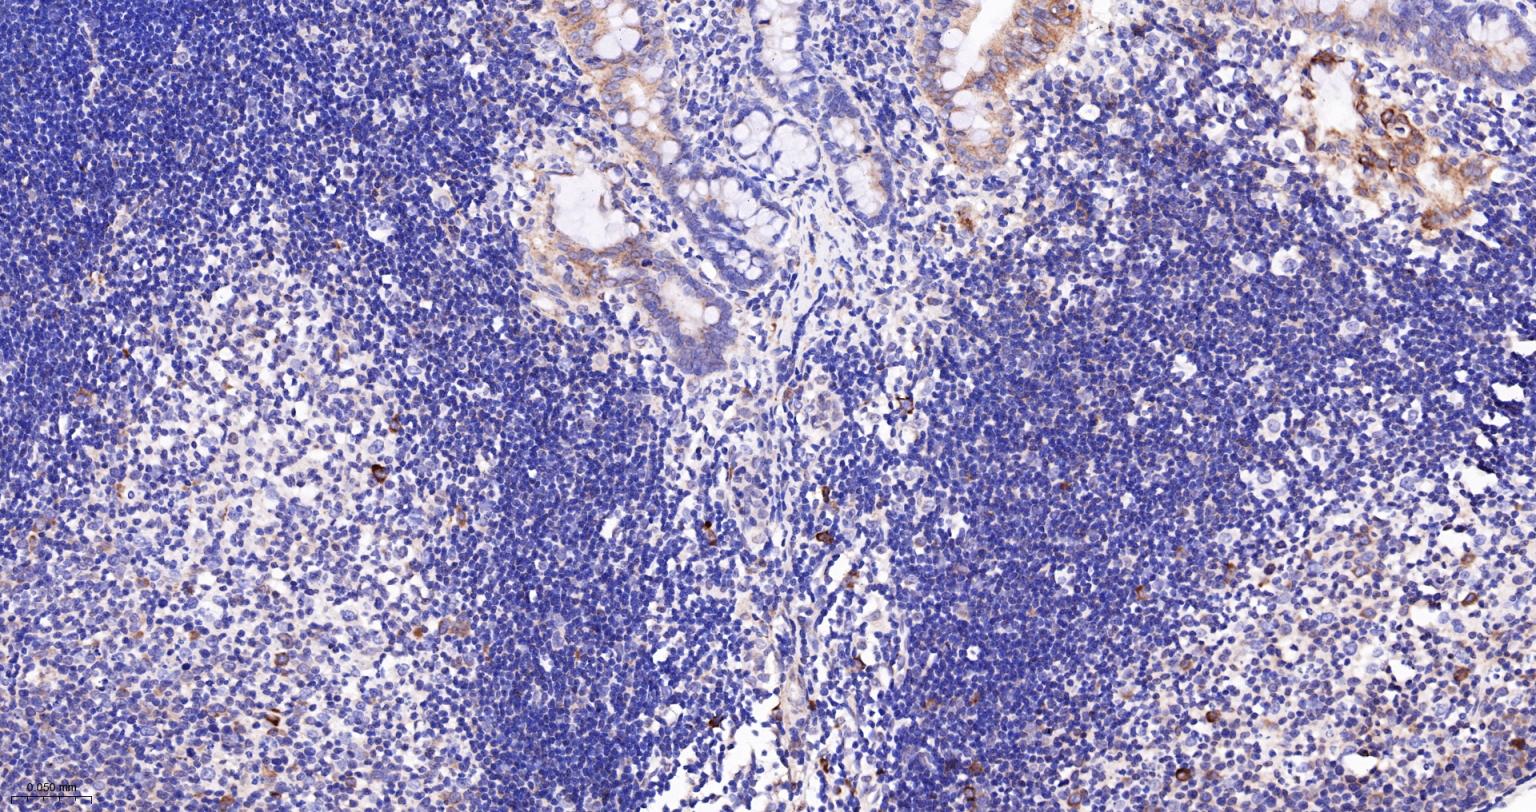

Paraformaldehyde-fixed, paraffin embedded Human Spleen; Antigen retrieval by boiling in sodium citrate buffer (pH6.0) for 15 min; The section was incubated with phospho-RPS6 (Ser235+Ser236) Polyclonal Antibody, Unconjugated (bs-3388R) at 1:400 overnight at 4°C, followed by conjugation to the bs-0295G-HRP and DAB (C-0010) staining.